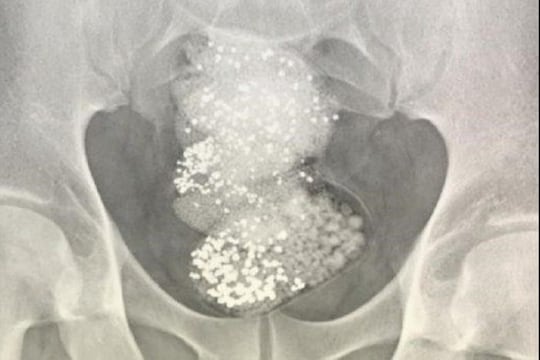

नवी दिल्ली, 10 जानेवारी : एखाद्या गोष्टीची तस्करी करण्यासाठी लोकं काय काय शक्कल लढवतील सांगता येत नाही. अशीच एक धक्कादायक बाब समोर आली आहे, ज्यात एका आफ्रिकेच्या चोरानं हिऱ्याची तस्करी करण्यासाठी पोटात 297 ग्रॅम हिरा चुरा करून लपवला. गल्फ न्यूजच्या वृत्तानुसार, ही घटना संयुक्त अरब अमिरातीची आहे, फेडरल कस्टम अॅथॉरिटीने (एफसीए) काही दिवसांपूर्वी एका व्यक्तीला अटक केले. या व्यक्तिनं चक्क हिऱ्यांचा चुरा करून तो खाल्ला. पोलिसांनी या चोराचा एक्स रे काढल्यानंतर यात हा धक्कादायक प्रकार समोर आला. वाचा- ‘मॅच जिंकला नाही तर…’, दिग्गज क्रिकेटपटूला पत्नीनं दिली धमकी; VIDEO VIRAL

वाचा- कॉलेजमध्ये विद्यार्थिनीच्या बॅगेत सापडली Lipstick, शिक्षकाने रॉडने केली मारहाण एक्स रे केल्यानंतर अधिकाऱ्यांना या प्रवाशाच्या पोटात 297 ग्रॅम कच्चा हिरा सापडला. ज्याची किंमत 90 हजार डॉलर (64 लाख रुपये) आहे. अहवालानुसार, त्या व्यक्तीने युएईमध्ये हिरासाठी संभाव्य खरेदीदार शोधले होते. त्याच्याकडे सध्या चौकशी केली जात आहे.